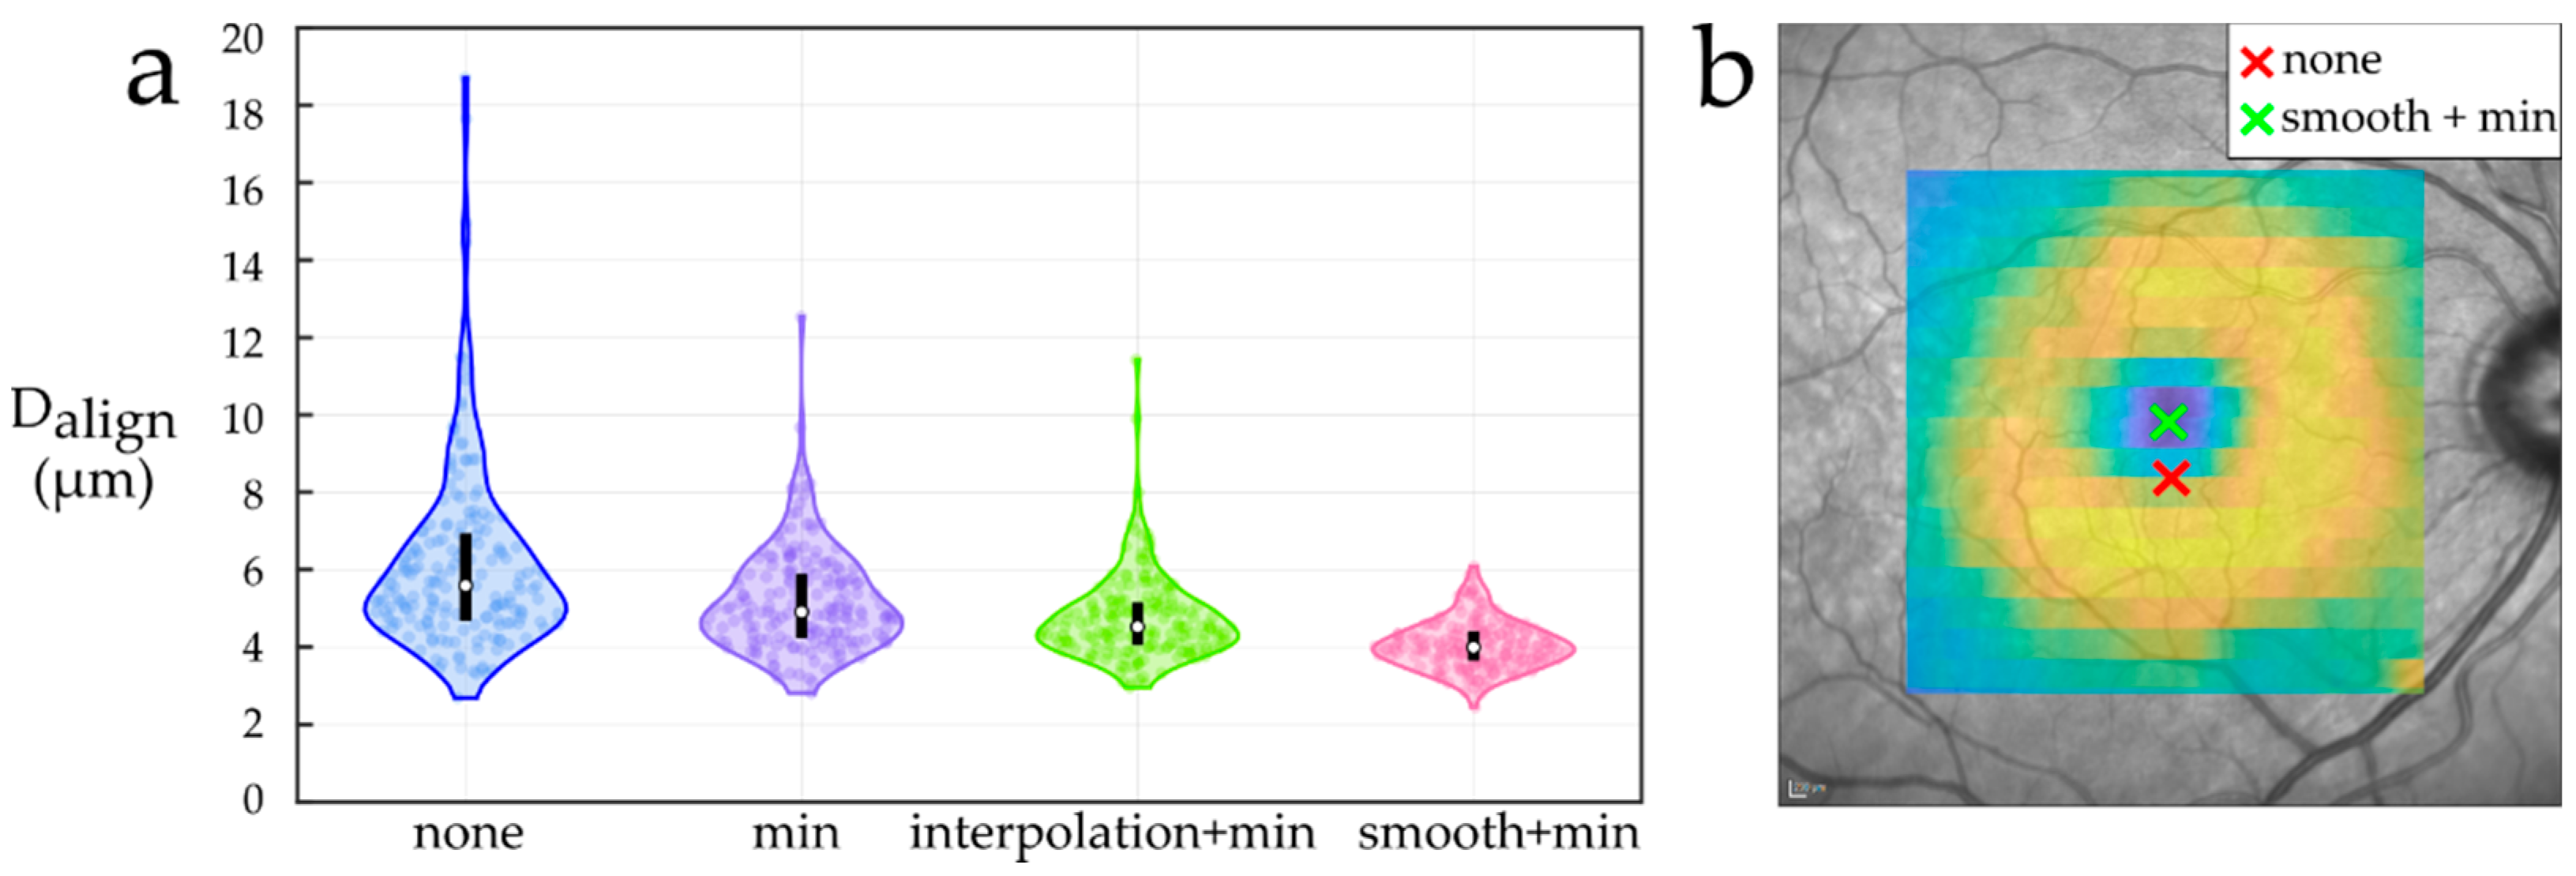

2.3.1. Foveal Center Location

- None: assume the center of the acquired scan as the foveal center.

- Min: locate the foveal center at the A-Scan point of minimum TRT in the central 0.85 mm radius region.

- Interpolation + min: resample the central part of the TRT map to a regular grid of 0.85 × 0.85 mm2 and a 0.02 mm spacing using cubic interpolation. Then, locate the foveal center at the grid point with minimum TRT.

- Smooth + min: resample the central part of the TRT map to a regular grid of 0.85 × 0.85 mm2 and 0.02 mm spacing, and smooth it before locating the foveal center at the grid point with minimum TRT. We used the implementation of AURA Tools (foveaFinder.m function) [44] to smooth the resampled TRT map by applying a filter with a 0.05 mm radius circular kernel.

2.4.1. Foveal Center Location

3.1. Foveal Center Location